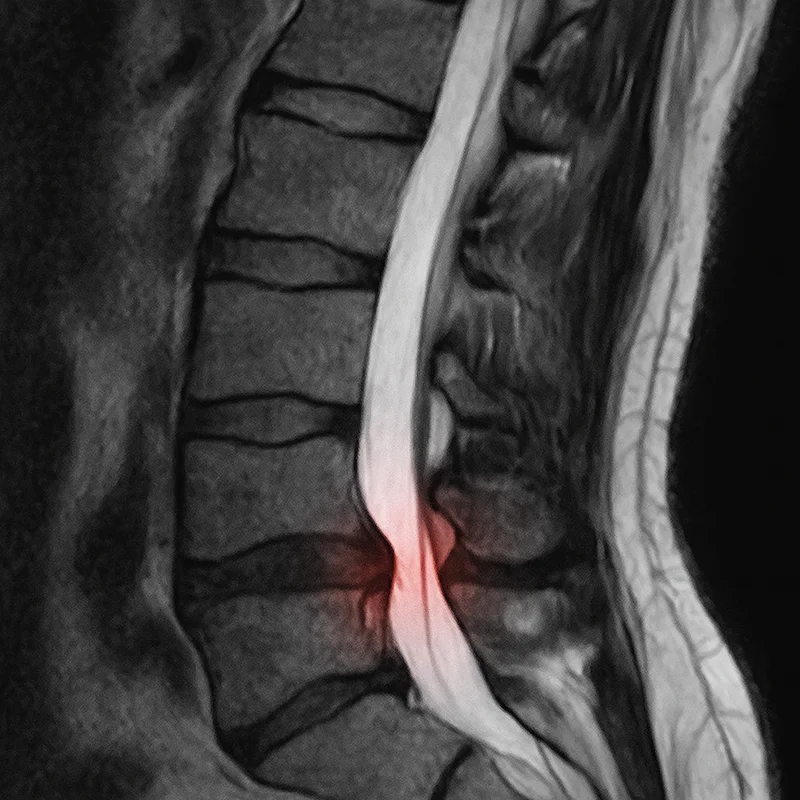

Herniated or bulging discs are the most frequent cause I see. The discs between your vertebrae act as shock absorbers. When a disc herniates, the soft inner material pushes outward and can press directly on a nerve root. I’ve written extensively about herniated disc treatment options if you want more detail on this specific cause.

In your back, pinched nerves most commonly involve the spinal nerve roots—the nerves branching off your spinal cord and exiting between each vertebra. These nerve roots are vulnerable because they pass through relatively tight spaces. Any narrowing of that space can cause problems.

Disc pressure reduction occurs with specific adjustment techniques and positioning. Proper spinal alignment takes pressure off damaged discs, allowing herniated material to migrate away from the nerve over time.